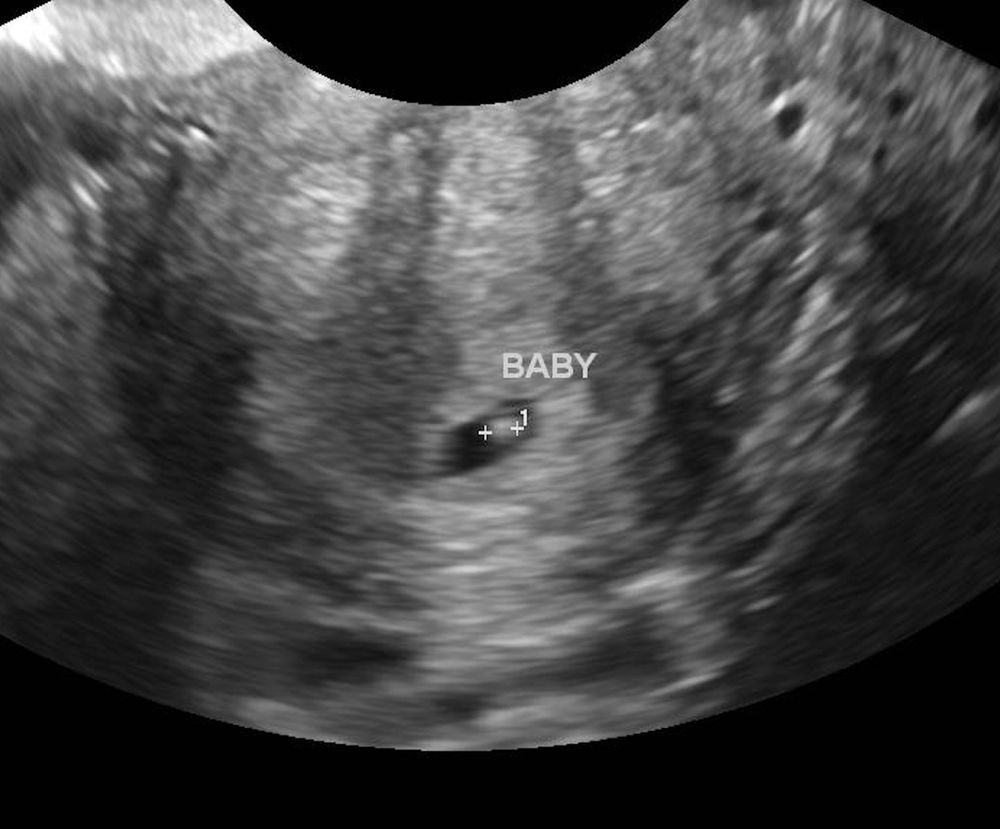

Маленькое плодное яйцо + фото

Первое узи с эмбрионом Мелкие кисты в цервикальном канале